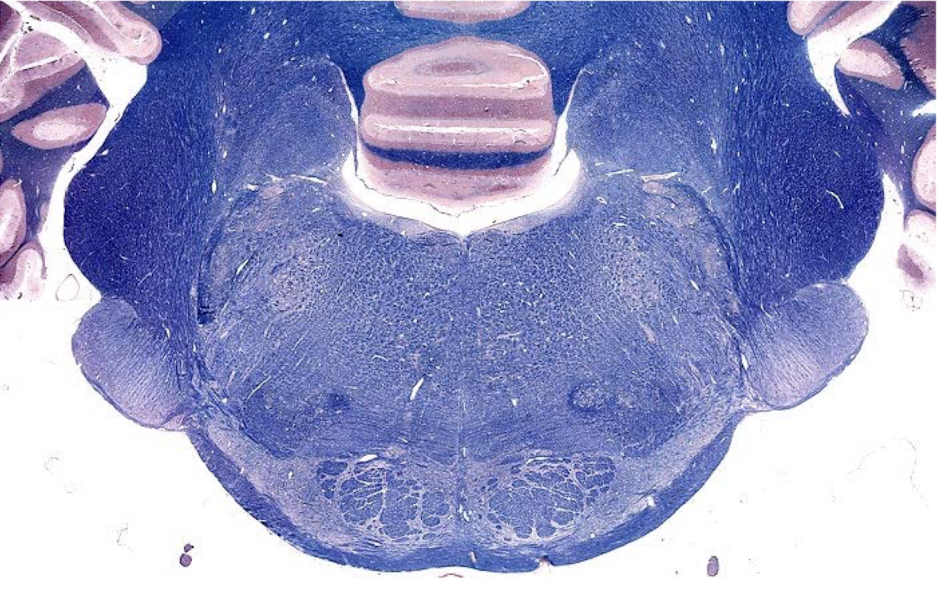

what section of the brain is shown?

pons

- closed 4th ventricle

- upside down muffin shape

- trigeminal nerve stump